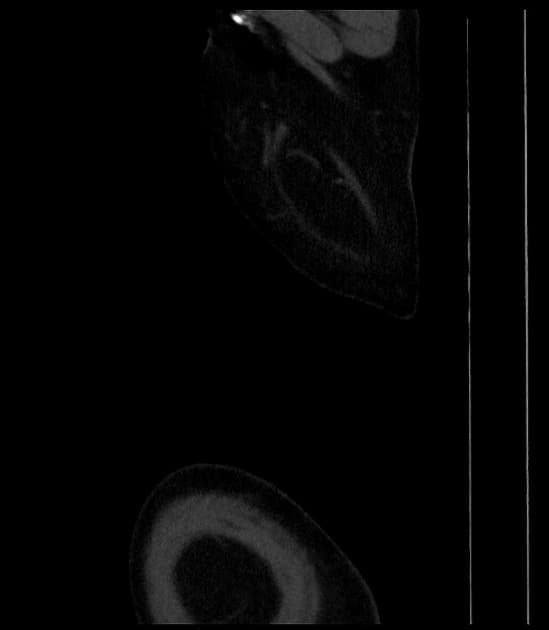

PSAX with color Doppler

Có vách nội mạc (intimal flap) ở vị trí xa hơn điểm xuất phát của động mạch dưới đòn trái, kéo dài xuống phía dưới, quan sát thấy trên mặt cắt qua hõm ức (suprasternal view).

Đây là một trường hợp điển hình của phân tách động mạch chủ (aortic dissection), hình ảnh thấy rõ sự tách lớp giữa nội mạc và trung mạc động mạch chủ, tạo thành lòng giả ở đoạn gần của động mạch chủ xuống (descending aorta). Trường hợp này thuộc type B Stanford / type III DeBakey. Tăng huyết áp là một trong những nguyên nhân phổ biến nhất gây phân tách động mạch chủ, đặc biệt ở bệnh nhân cao tuổi.

- "Siêu âm tim có thể phát hiện vách nội mạc và lòng giả, đặc biệt ở đoạn xuống của động mạch chủ qua mặt cắt qua hõm ức."